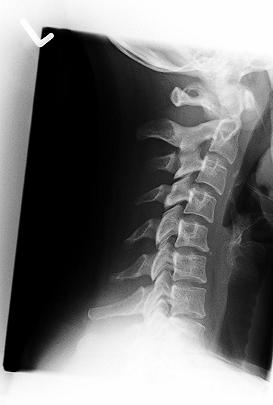

Hallo zusammen...ich bin Melissa, 28 aus dem schönen Emsland. Ich habe seit langer Zeit Probleme mit dem Rücken. Sprich LWS sowie HWS. Ich habe im Lendenwirbelbereich starke Schmerzen, die mittlerweile bis ins rechte Bein ausstrahlt. Dazu habe ich starke Nacken und Kopfschmerzen und Kribbeln in der rechten Hand. Ich habe immer wieder KG und Massagen bekommen. Das brachte aber nur für den Moment Linderung. Dort wurde mir vom Therapeuten geraten, mal ein Röntgenbild machen zu lassen. Termin beim Orthopäden, Gespräch und dann ab zum Röntgen. Der Orthopäde ist, muss ich dazu sagen, sehr "sonderbar", hat immer stumpfe Sprüche auf Lager. Leider gibt es hier oben nicht eine große Auswahl an Fachärzten. Er erkannte dann wohl auf den Röntgenbildern, dass ich am Morbus Scheuermann leide und verkrümmungen der Wirbelkörper und der unteren LWS habe. Auch das Bild der HWS war wohl nicht ganz okay und er meinte es seinen 3 Bandscheiben schon "extrem dünn" und auf Dauer könne man einen Vorfall nicht verhindern. Er veranlasste kein MRT und meinte nur : "Tja ich kann ihnen ja kaum eine neue WS einsetzen."

So nun war gestern endlich mein MRT Termin. Sitze nun schon den ganzen Morgen vorm PC und durchstöbere das Netz um Bilder zu vergleichen. Leider habe ich null Ahnung wie es da aussieht, ob dass alles so sein muss etc. Irgendwie bin ich dann auf dieses Forum gestoßen. Ich lade euch jetzt erstmal ein paar Aufnahmen hoch. Vlt könnt ihr ja was drauf erkennen

Zur HWS: Veränderunge sind zu erkennen, wenn auch nicht so extrem.

Generell gilt aber auch hier: die Bilder sind zu klein, um sie objektiv beurteilen zu können. Dies geht nur "live", am besten mit den Rö-Folien in der Hand.